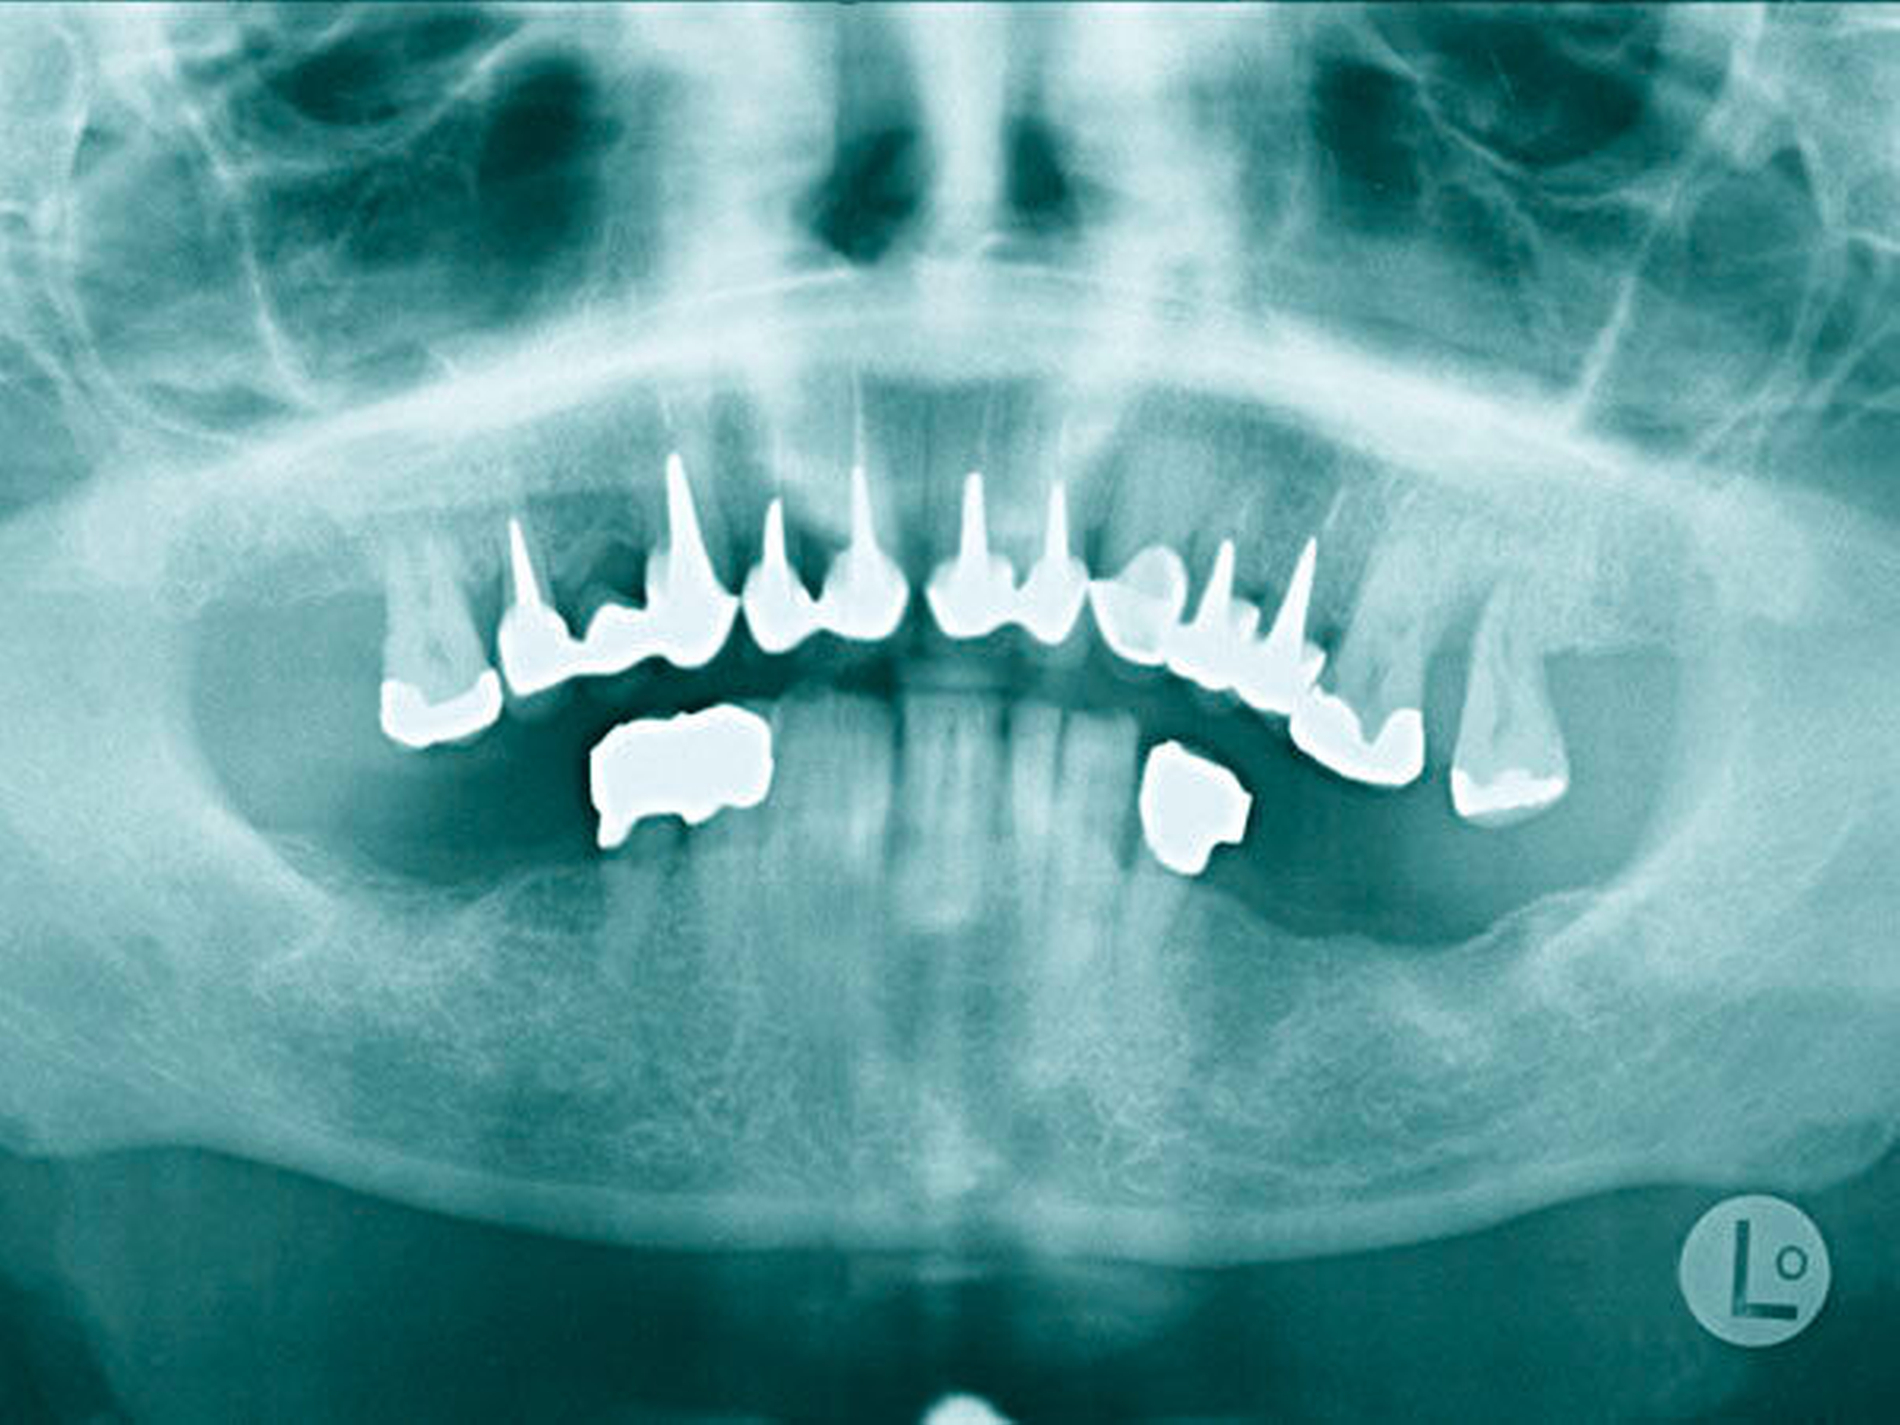

Der Plaqueindex PCR betrug 72 Prozent [O`Leary TJ et al., 1972] und der gingivale Blutungsindex GBI 75 Prozent [Ainamo J et al., 1975]. Das alio loco angefertigte Orthopantomogramm (Abbildung 3) zeigte horizontalen Knochenabbau bis zu einem Drittel der Wurzellänge in beiden Kiefern. Die Zähne 16 und 26 wiesen einen Knochenabbau > 2/3 der Wurzellänge auf. Am Zahn 27 mesial erreichte der Knochenabbau die Wurzelspitze; zudem war der Zahn elongiert und wies eine Kippung nach distal auf. In einer ersten Einzelzahnprognose wurden alle Zähne mit Ausnahme von Zahn 27 als sicher eingestuft. Prothetisch war die Patientin im OK mit einer Brücke (13 bis 15), Kronenblöcken (21/11, 21/22, 24/25) und Amalgamfüllungen an den Zähnen 16 und 26 sowie im UK mit einer geschiebeverankerten Modellgussprothese versorgt.